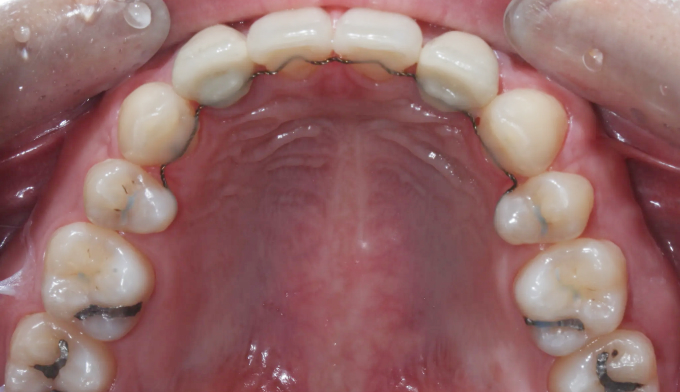

돌출감과 가지런하지 못한 앞니, 그리고 어금니의 교합이 좋지 않은 경우입니다.

좌측 아래 작은어금니가 빠진이 오래되었기 때문에, 균형을 맞추기 위해 반대편 작은어금니를 발치하여 돌출감을 해소해주었습니다. 나왔던 입이 들어가면서 턱 라인이 개선되었고, 입을 다물때도 보다 더 편안하게 되었습니다.

교정전부터 변색되어있던 양쪽 앞니는 미백과 보철치료를 동반하여 교정종료 후 개선하였습니다.

총 교정치료는 22개월입니다.